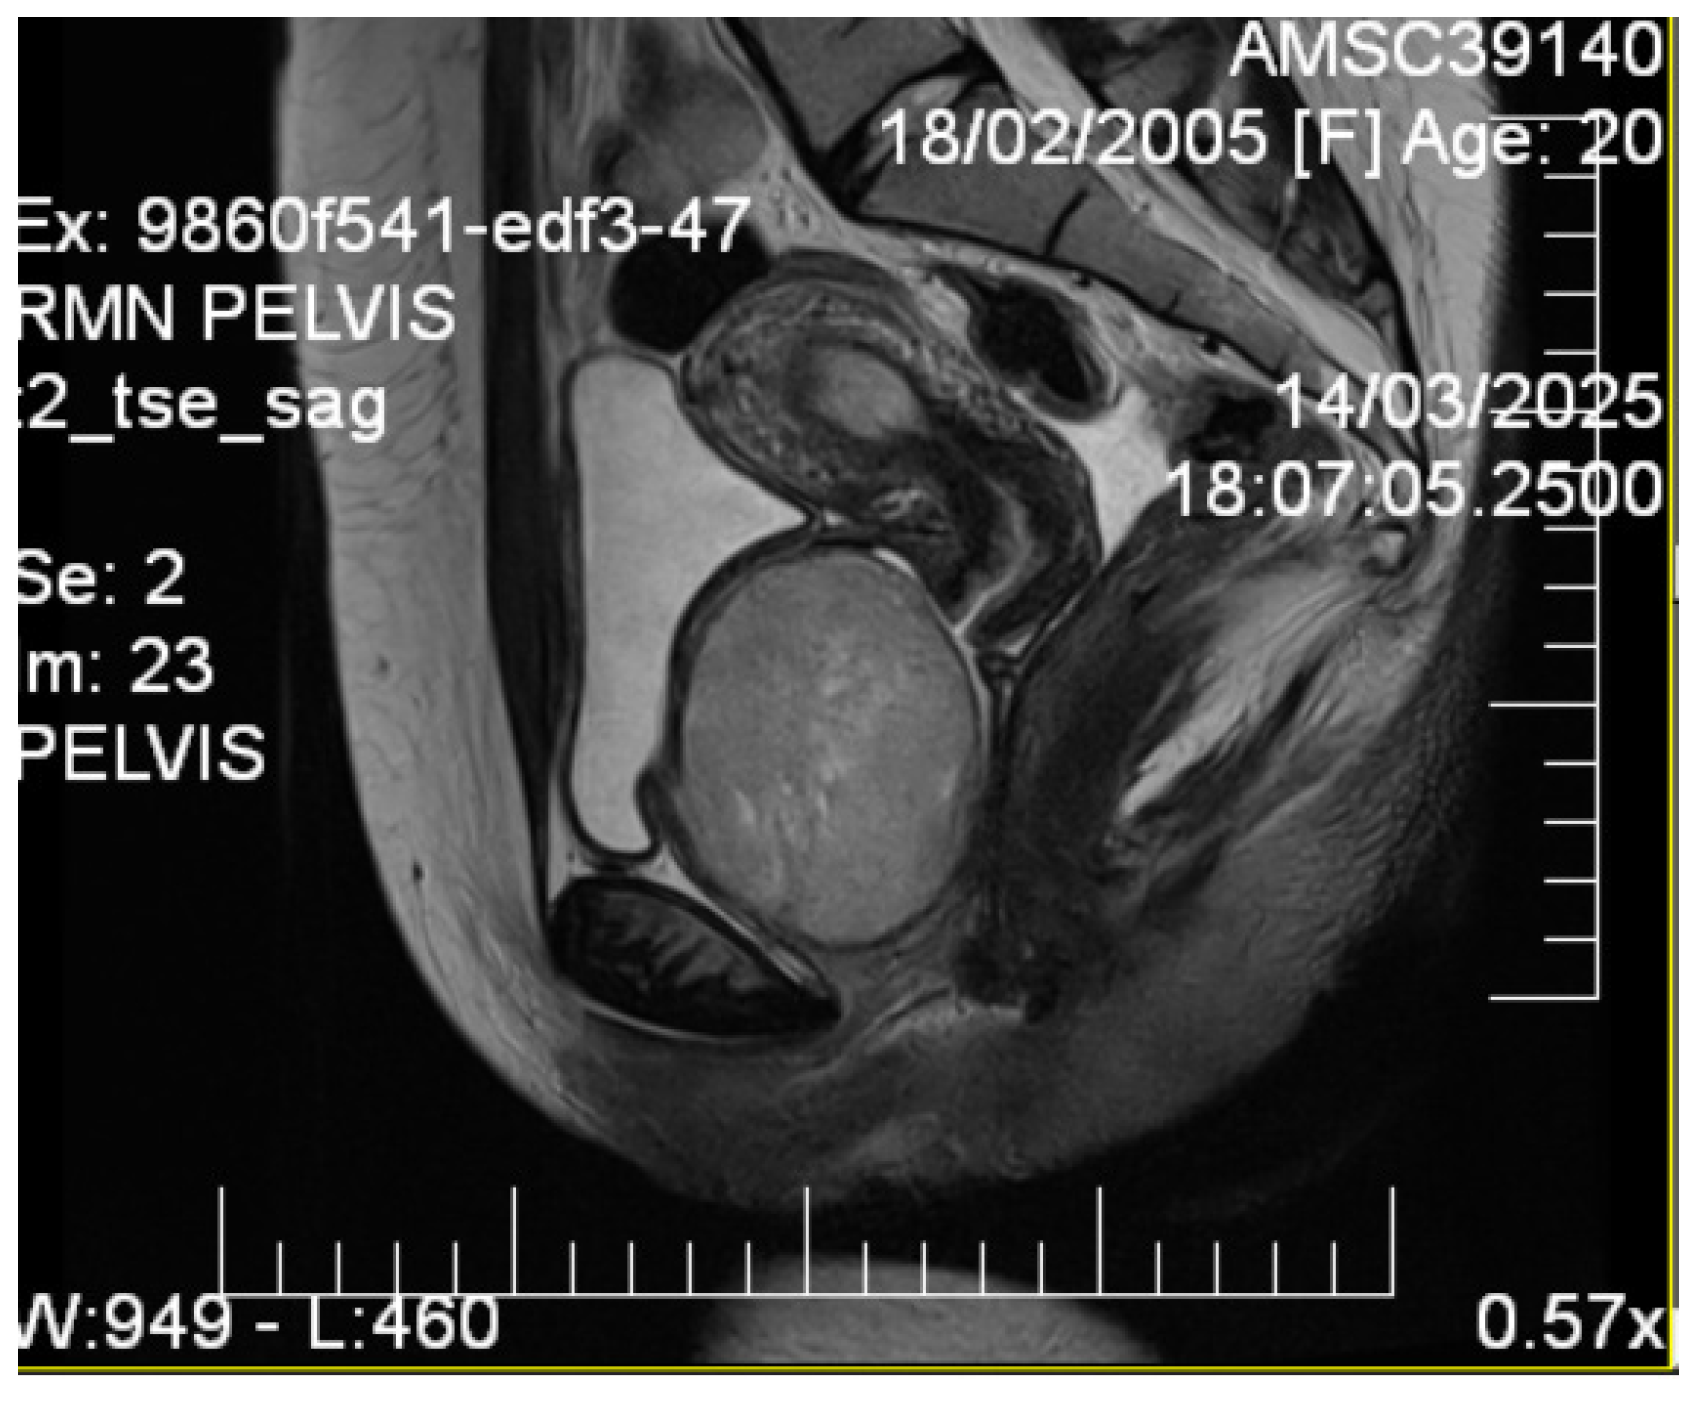

Given the patient’s young age and solid mass characteristics raising concern about malignancy, comprehensive magnetic resonance imaging (MRI) was performed using a 1.5-Tesla scanner with multiplanar sequences (General Electric, Cluj-Napoca, Romania). The MRI demonstrated signal intensity patterns highly suggestive of leiomyoma: isointense to muscle on T1-weighted imaging, markedly hypointense on T2-weighted imaging (characteristic of leiomyoma due to high fibrous content), restricted diffusion with high ADC values of 0.9 × 10−3 mm2/s (b-values: 0, 1000 s/mm2) consistent with benign leiomyoma, and homogeneous enhancement following gadolinium administration. In the literature [12], benign leiomyomas typically demonstrate ADC values in the range of 0.8–1.2 × 10−3 mm2/s, atypical leiomyomas may overlap, but are often slightly lower (0.7–1.0 × 10−3 mm2/s), while leiomyosarcomas tend to show more pronounced restriction, often <0.8 × 10−3 mm2/s. These ranges overlap, highlighting that although MRI provides highly suggestive features, histopathological confirmation remains essential. MRI also confirmed the septate uterus and showed detailed anatomical relationships (Figure 3 and Figure 4).

Figure 4.

Sagittal T2-weighted pelvic MRI. A T2-hypointense, well-circumscribed lesion (measuring ~7 cm) is observed in the vesicovaginal space. The lesion displaces the bladder anteriorly and the vagina posteriorly, maintaining clear margins with adjacent pelvic structures. Diffusion-weighted imaging demonstrated restricted diffusion with an ADC value of 0.9 × 10−3 mm2/s. The signal characteristics were consistent with a leiomyoma.